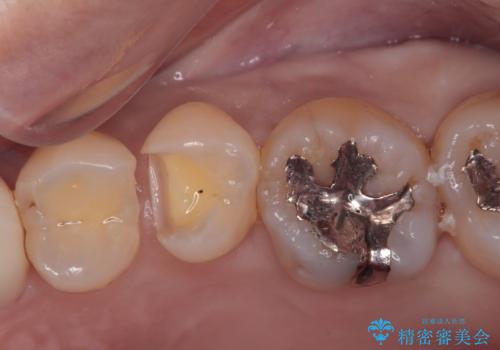

虫歯がないか確認し、セラミックインレーにて修復することになりました。

セラミックインレー装着時には、唾液の侵入を防ぐために、ラバーダム防湿を行いました。

ラバーダム防湿を行い、セラミックの接着をすることで、唾液や血液などの接着阻害因子を排除することができます。